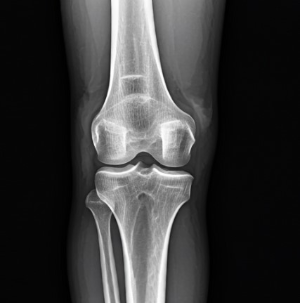

50대는 관절 건강을 관리하는 데 있어 중요한 전환점입니다. 건강보험심사평가원의 통계에 따르면, 무릎관절증으로 병원을 찾는 50대 환자 수가 40대에 비해 무려 3배 이상 증가한다고 합니다. 이는 단순한 숫자가 아닌 우리 몸이 보내는 경고 신호로 이해해야 합니다.

특히 계단을 내려갈 때 무릎에 더 큰 부담이 가해져 통증이 심해질 수 있습니다. 이는 무릎 연골이 약해졌거나 손상되었음을 시사합니다. - 오랫동안 앉아 있다가 일어날 때 느껴지는 뻣뻣함

관절에서 '딸깍' 소리나 '삐걱' 소리가 자주 들리는 것은 관절 간 마찰이 증가했음을 나타낼 수 있습니다. 이는 연골의 손상이나 관절액 부족과 관련이 있습니다. - 가벼운 운동 후에도 오래 지속되는 통증